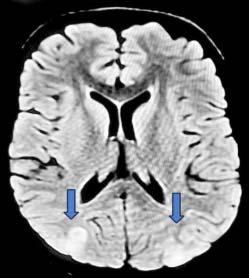

The model (Fig 1) has a classification ability of 80% (Area under ROC curve), with cut off value of 4.5 with 84.1 % sensitivity and 55% specificity. Therefore, a cut off score of 4 was chosen. A total score of <4 suggested Dengue, and >4 suggested Scrub Typhus.

This model was applied to another subset of patients, with 25 patients in each group for both Dengue and Scrub Typhus, and the results were obtained as mentioned in Table 2. The sensitivity was 72% and 48% when applied on patients who were tested positive for Dengue and Scrub Typhus respectively.

1 — ROC curve of age, hemoglobin, TLC, NLR, platelets, total

CRP, albumin and altered sensorium